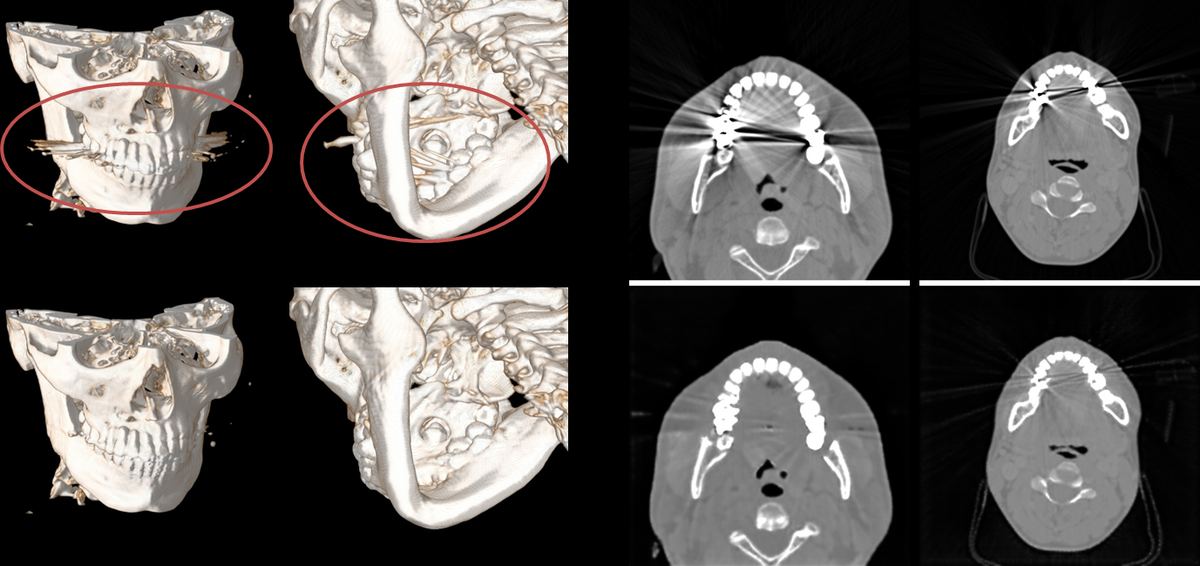

典型症例 ― 頭部・顎骨CT における金属アーチファクト(赤マーカー部)

顎骨CT 金属アーチファクト典型症例

BEFORE(従来)

平均 33分

熟練者による手作業修正 / 1症例

AFTER(D-MAR)

数分以内

AI自動処理 / 処理時間1/10以下